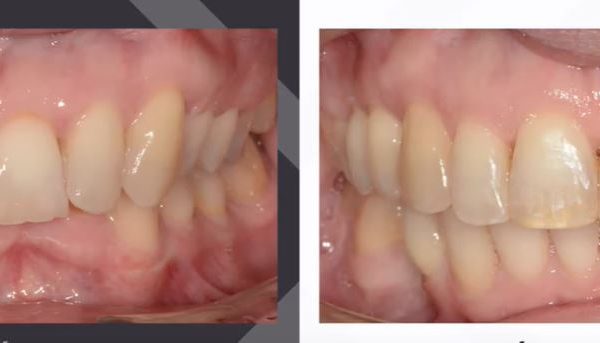

Az elmúlt évekből rengeteg szakmai referenciát tudnánk bemutatni, amelyek különböző fogszabályozási problémákat oldottak meg. Válogatva a több száz esetből, ezen az oldalon olyan képeket, információkat igyekeztünk bemutatni, amelyeknek a segítségével a jövőbeni pácienseinknek azt tudjuk üzenni: A Te fogsorod is lehet gyönyörű!

(Képeket a Pácienseink külön írásos beleegyezésével mutatjuk be!)